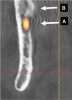

Inferior Alveolar Canal

Proceeding anteriorly, the inferior alveolar nerve (IAN) (Figure 2) may descend gently or steeply in the mandible.8 The canal is usually around 3.2-mm wide and surrounded by cortical bone, which does not reliably provide resistance to a twist drill.9 In order to determine the length of a dental implant at a specific site in the posterior mandible, it is advisable to measure from the crest of the alveolar bone to the coronal aspect of the IAN and subtract 2 mm to provide a safety zone.10